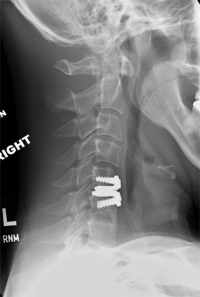

(Click to Enlarge Image) These are two Prestige LP artificial discs implanted in the front of the neck. You can see the “keels” imbedded in the bone and the small “rings” on either side of the disc that stabilizes these implants